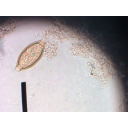

Trứng thường màu vàng, vỏ dày, hình bầu dục, hai đầu có hai nút.